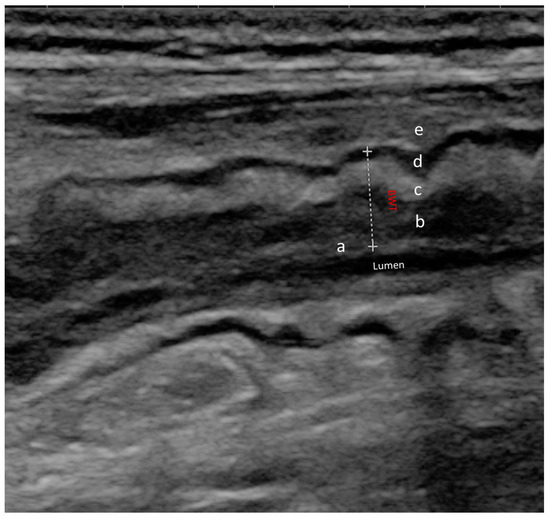

Together with the increasing diffusion of IUS in IBD, the knowledge of sonographic signs of active disease has improved. Several ultrasonographic parameters are nowadays recognized as being associated with intestinal inflammation, including bowel wall thickness (BWT), mural and extramural changes, and variation in bowel wall flow (BWF). Figure 2 shows the normal wall structure. BWT increases as a direct expression of wall inflammation, especially in CD, due to the transmural nature of the disease [7]. Furthermore, a distortion of the normal wall architecture may be present in active disease, as may the presence of increased vascular signals and direct signs of neo-angiogenesis related to disease activity [16]. In particular, the latter is measured with Doppler ultrasonography, and the most frequently used score is the Limberg score, which provides a semi-quantitative characterization, categorizing the vascularization of the wall from 0 to 4 [17]. Finally, alterations of the mesenteric adipose tissue can be observed in IBD. Most frequently, a proliferation of mesenteric adipose tissue can be seen around the affected intestinal loops [16]. Among the different IUS parameters used to assess disease activity, BWT proved to be the most reliable. A threshold of BWT ≥ 3 mm has been established in both CD and UC to distinguish between active and quiescent disease [18]. In a recent meta-analysis and systematic review by Sagami et al., this cut-off showed pooled sensitivity and sensitivity in detecting disease activity of 86.4% and 88.3%, respectively [19].

Figure 2.

Normal ultrasound bowel wall stratification The bowel wall is composed of five different layers with different echogenic patterns. In order from the innermost to the outermost layer, we can observe: (a) mucosa-lumen interface; (b) muscolaris mucosae; (c) sub-mucosa; (d) muscolaris propria; (e) serosa and extramural structures (peritoneum, fat); BWT (dotted line) is the distance between the lumen-mucosal interface and the serosa.